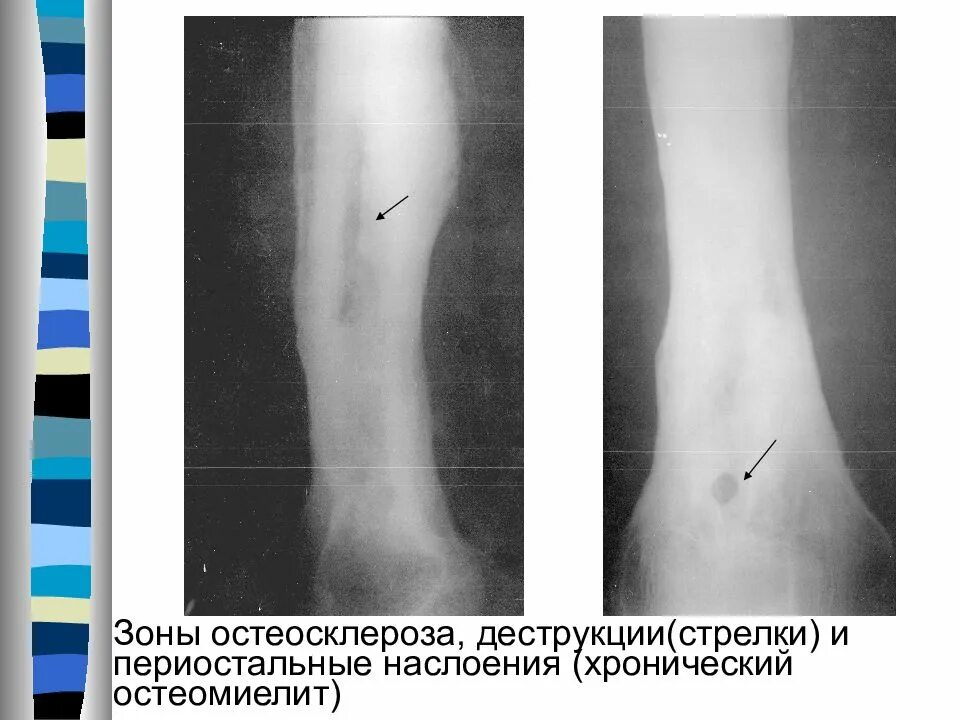

Зона деструкции